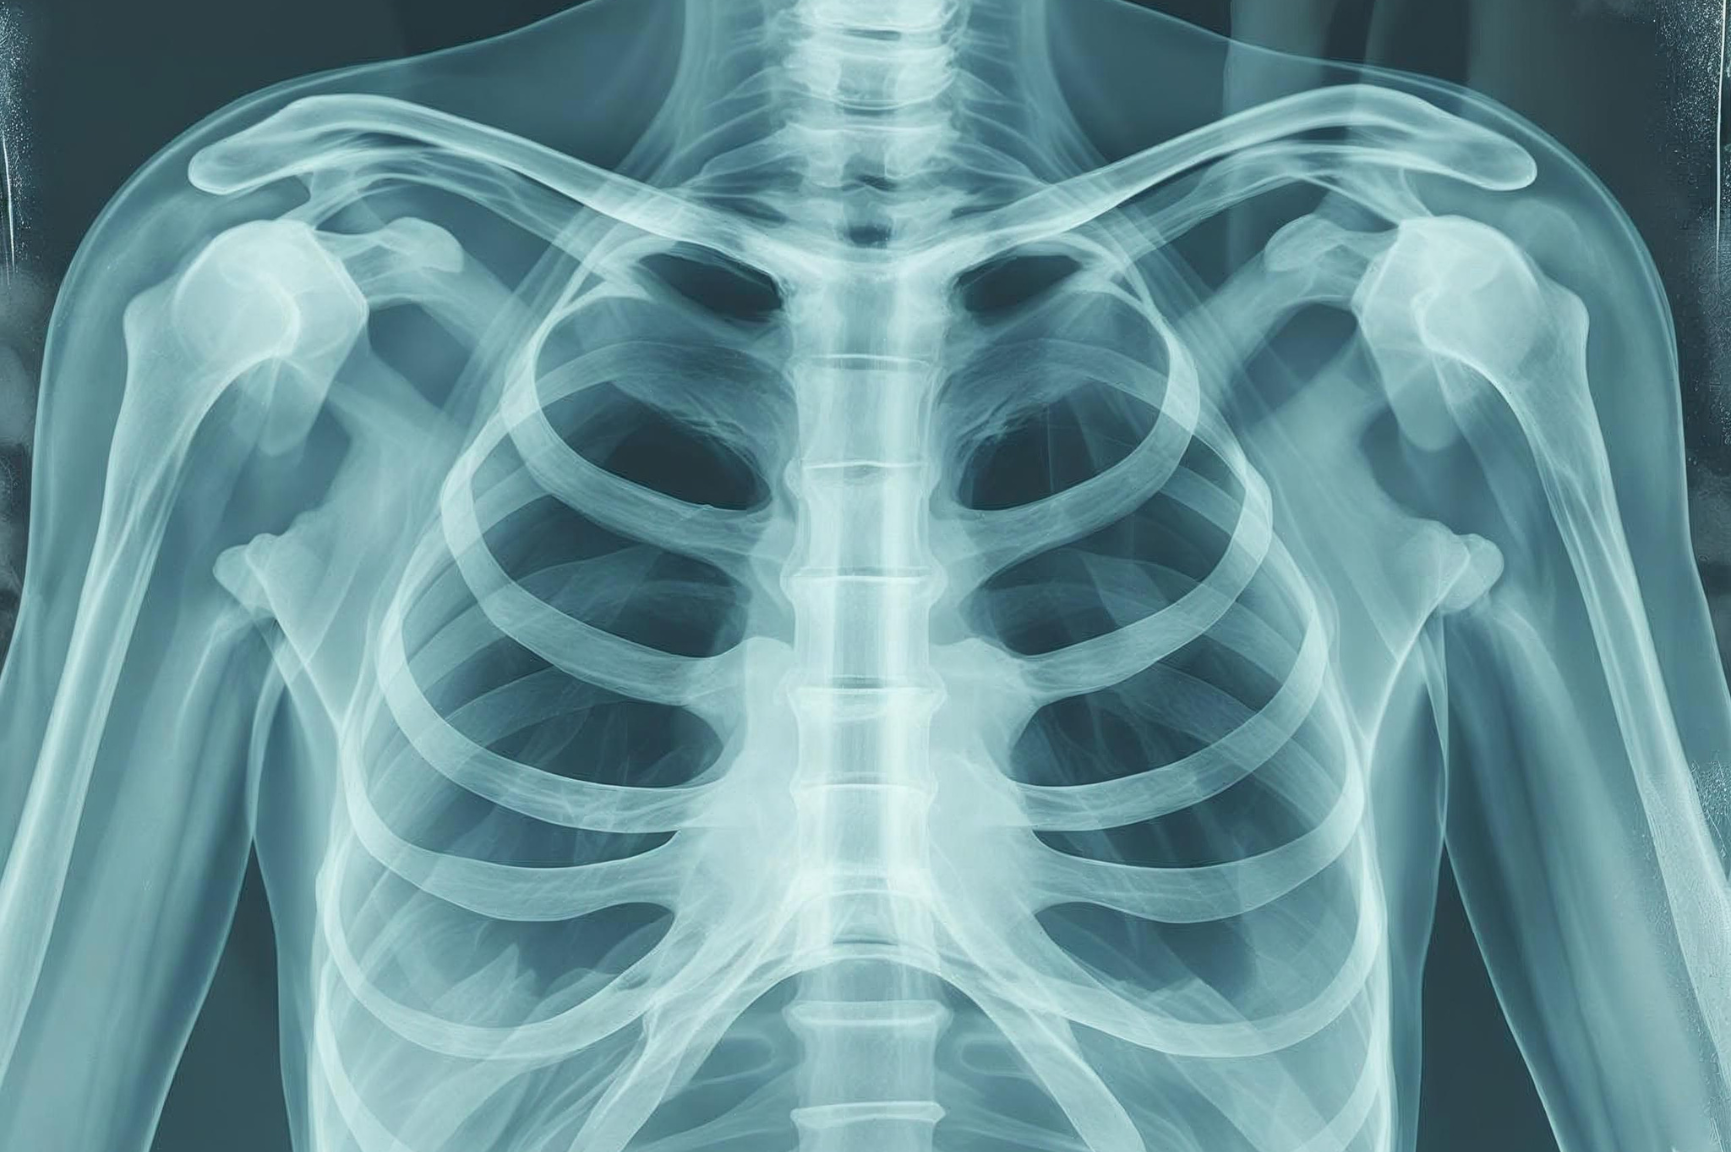

Interventional Radiology (IR) uses advanced imaging technology to diagnose and treat conditions from inside the body—without the need for large incisions or traditional surgery.

X-rays – For visualizing blood vessels and guiding vascular procedures